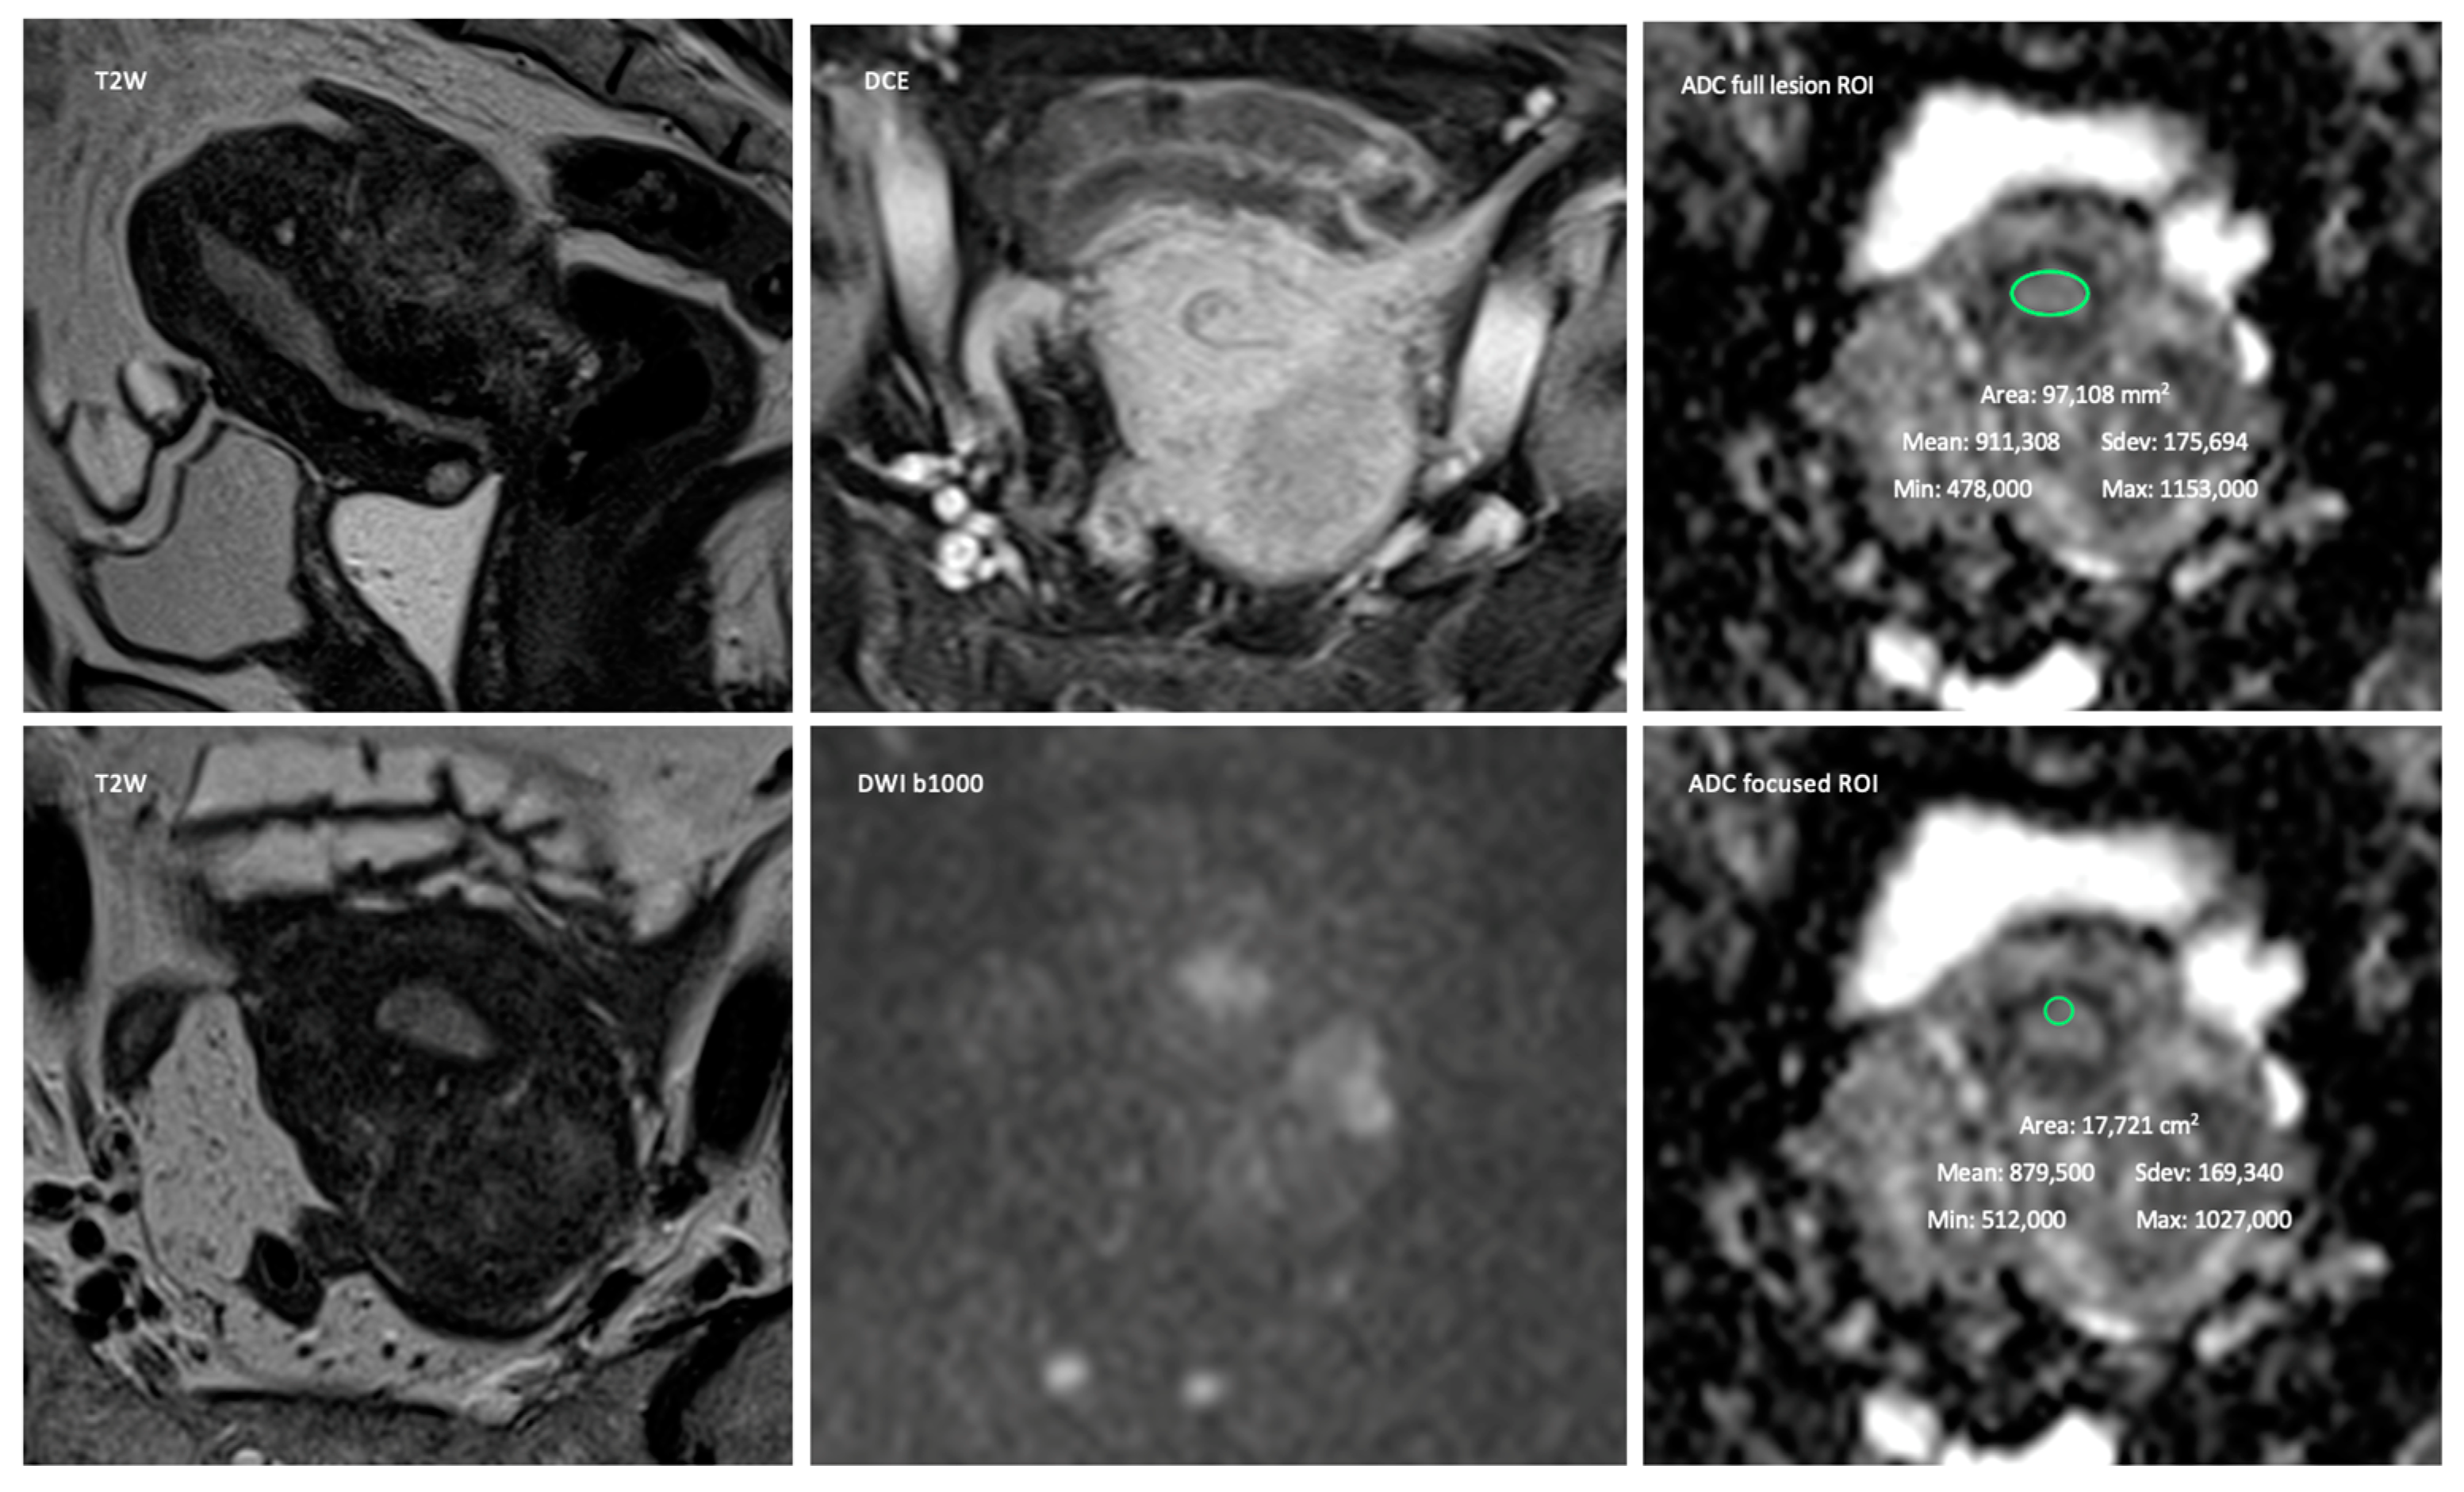

1. Introduction

2. Materials and Methods

2.2. MR Imaging

2.3. Image Interpretation